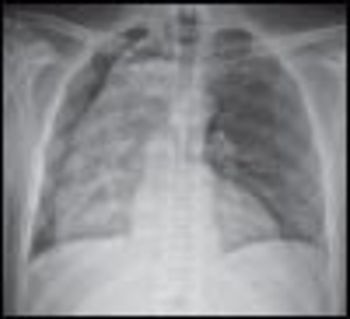

Phrenic nerve paralysis can present with chest wall pain, cough, and exertional dyspnea mimicking cardiac dyspnea. Fluoroscopy is the most reliable way to document diaphragmatic paralysis, and the sniff test confirms that abnormal hemidiaphragm excursion is due to paralysis rather than unilateral weakness.